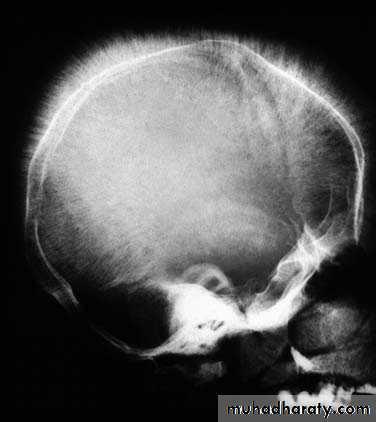

• • Skull radiographs showing hair-on-end appearance due to widening of diploic spaces